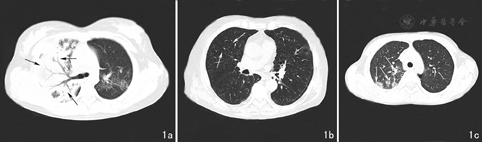

儿童组20例,CT影像表现以大片状实变影为主(图1a),磨玻璃样变和小斑片状实变影明显低于成人组;成人组16例,CT影像表现以磨玻璃样变(图1b)和小斑片状实变影(图1c)为主,大片状实变影、肺不张、淋巴结肿大、胸膜腔积液和支气管血管束增粗、支气管扩张则明显低于儿童组。儿童组与成人组支原体肺炎CT影像表现之间差异均有统计学意义(P<0.05)。见表2。